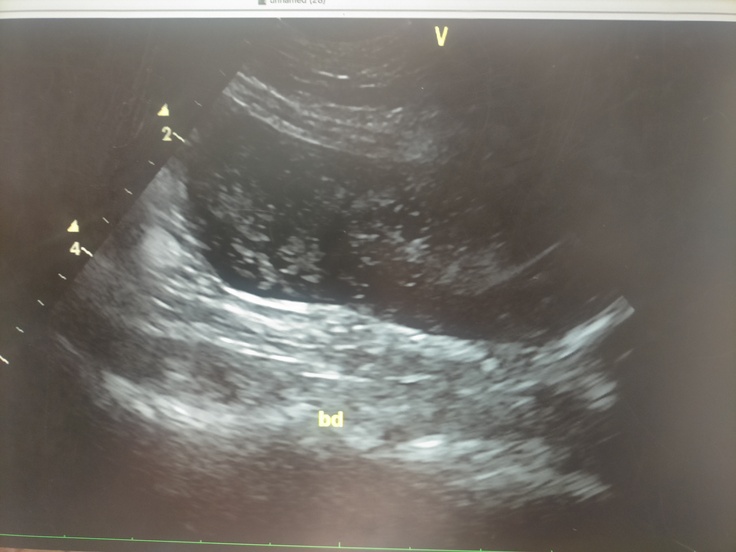

ただ、膀胱にまた謎の白モヤが沢山あり(本来は真っ黒で写る)今回も脂肪説が濃厚ではあるものの、男の子なのでそもそも結石等が出来るリスクも高いし、以前特に利尿器系のトラブルはないのに炎症が起きていて、膀胱に浮遊物(ふわ~と動くので、今日のとはまた違う)が写っていたこともありお薬を飲んだり…なんて経緯もあるので、

定期的に尿検査もしていこうね!と💉

でも全体的にとにかく元気に過ごしてくれていて、過去のエコー検査データを見比べる為に4月頃のを先生と一緒に見ていたのですが、

この頃はまだまだ腫瘍があって、リンパ節の部分に印がついていて…